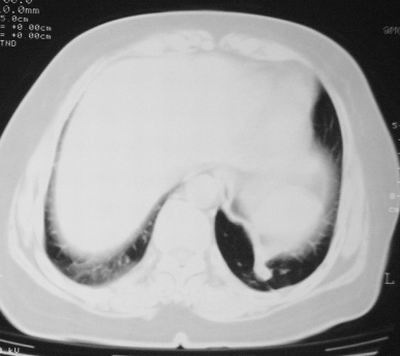

患者,女,64岁,4年前左腮腺"多形性"腺瘤手术治疗史.现复查胸部ct见左下肺块状影,该影与原左腮腺手术是否有联系?

本次复查胸部ct

左下肺癌伴左肺门淋巴结转移

支持考虑左下肺原发性肺癌,并左肺门淋巴结肿大

左下周围型肺癌伴左肺门淋巴结及右肺转移可能性大.

左下肺后基底段实性肿块,周围有毛刺,病变周围有肺气肿,与降主动脉间有条带状影相连,病灶4年前查体发现,纵隔内未见肿大淋巴结。考虑.肺隔离症,建议增强扫描与周围型肺癌鉴别。